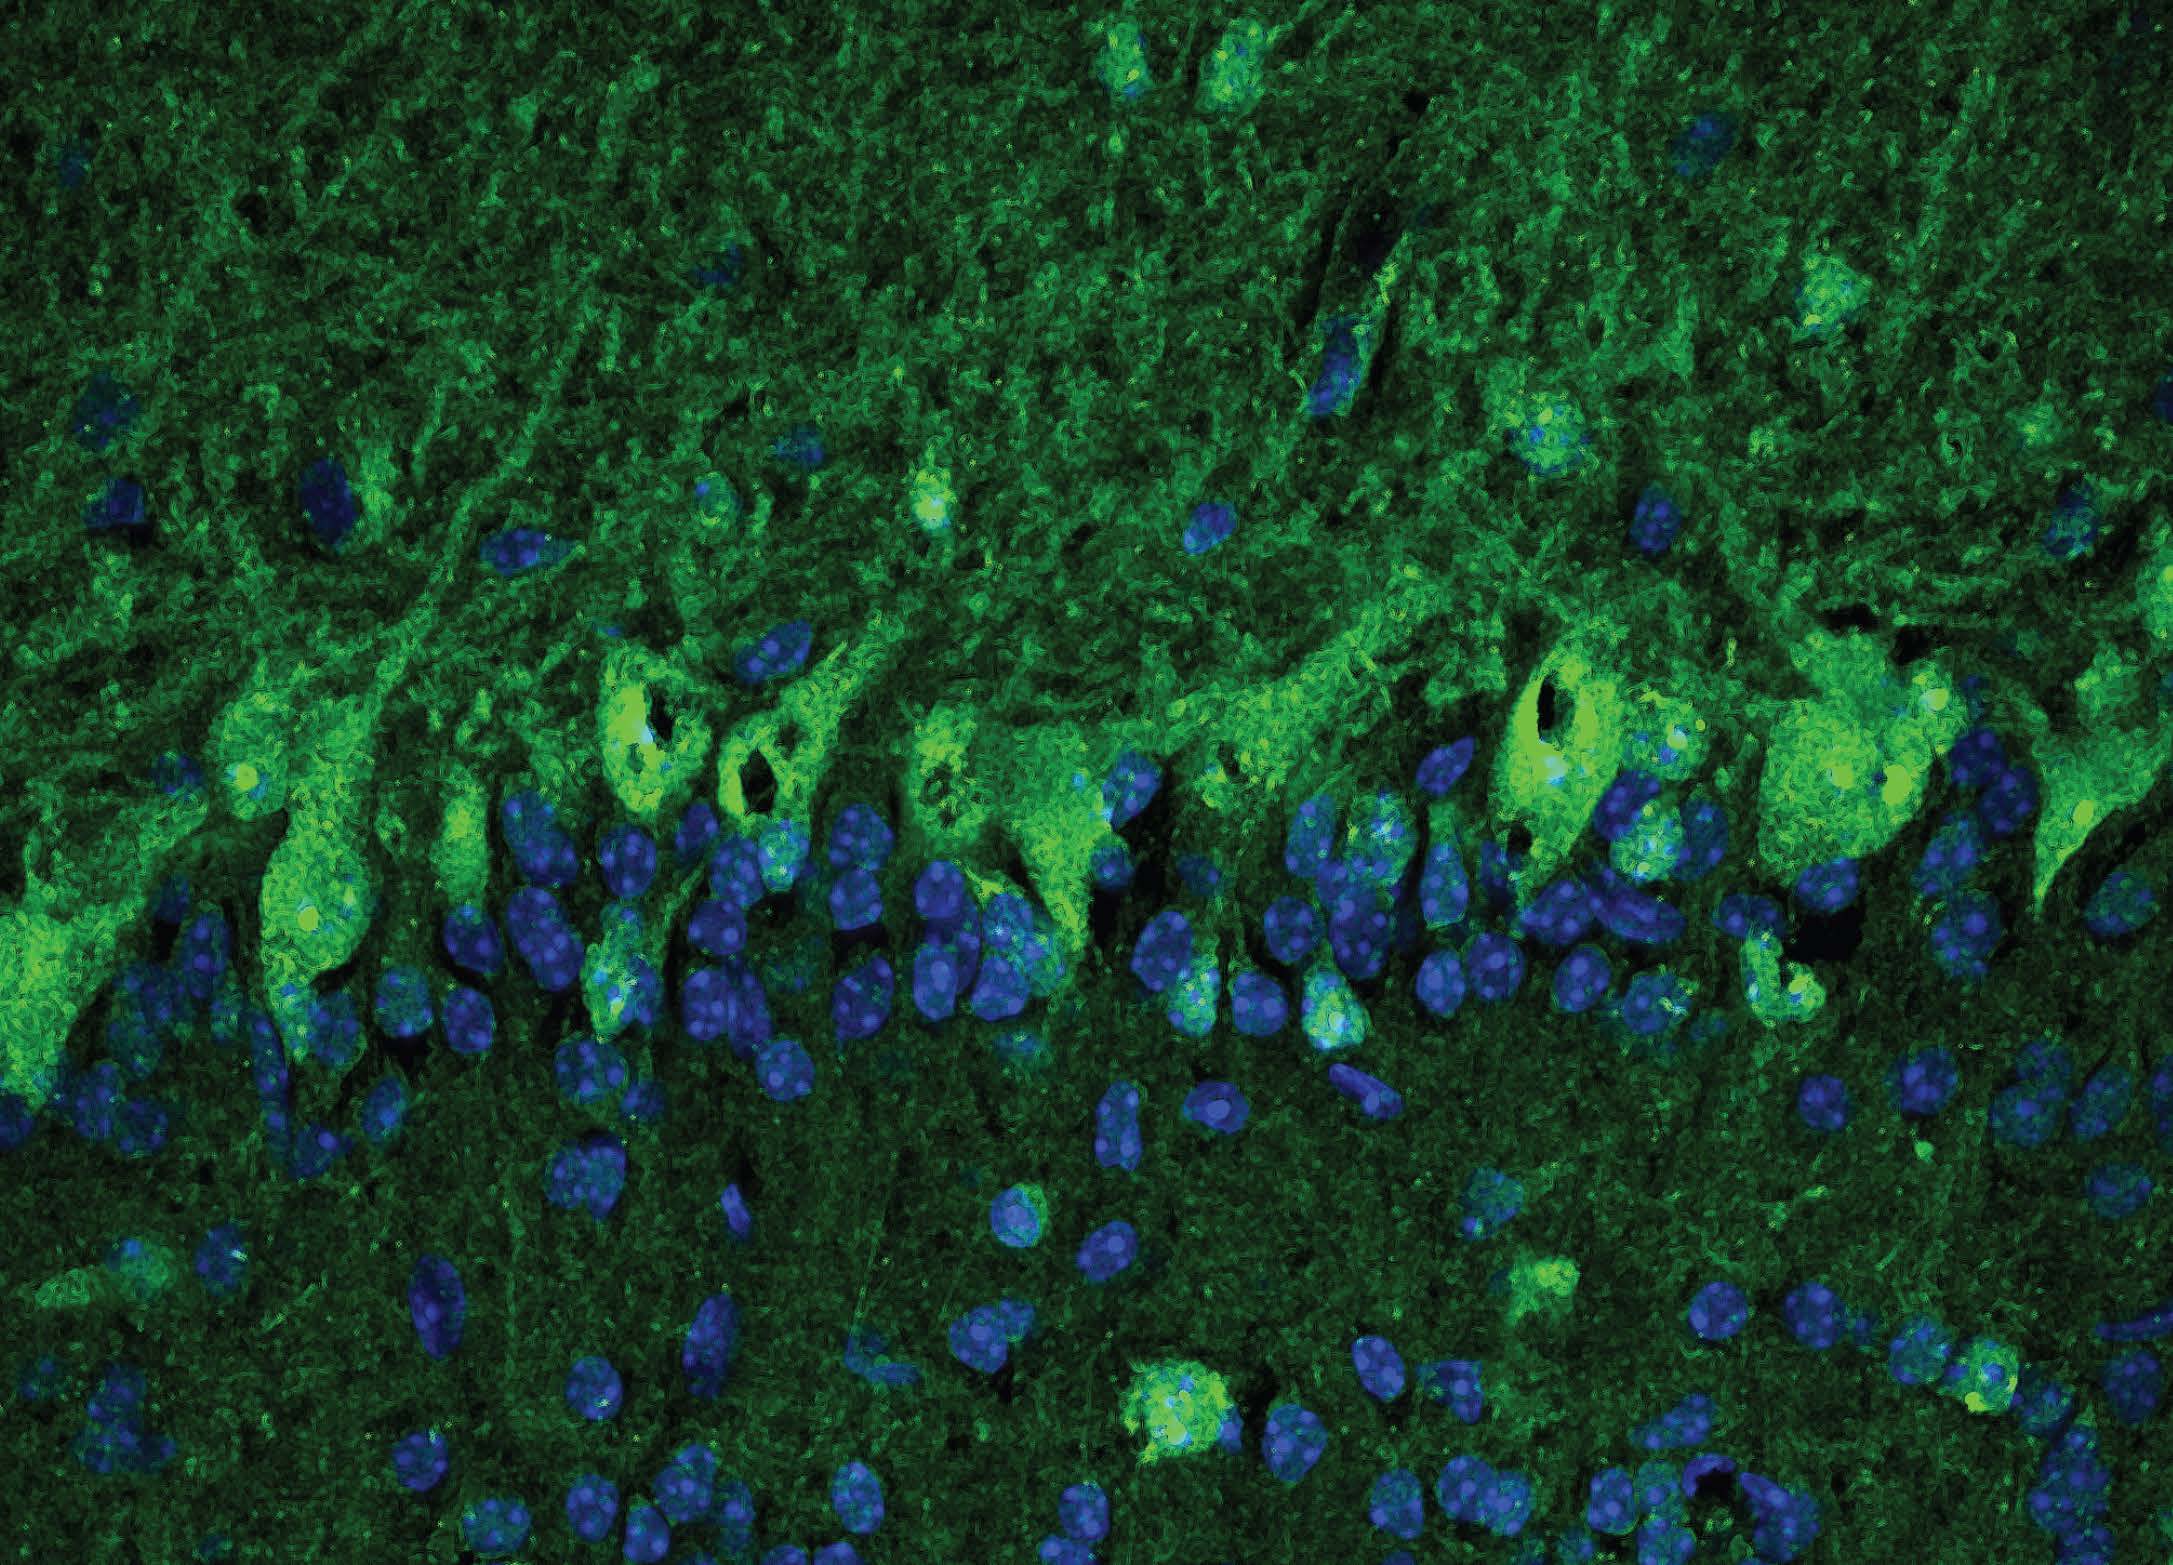

Image of the olfactory bulb. The green in the image shows immunostained cerebrospinal fluid from one patient containing neural autoantibodies. Image credit: Bartley CM et al. JAMA Neurology

The researchers examined the patients’ cerebrospinal fluid, obtained via lumbar puncture, and found that two of the patients, both of whom had histories of unspecified depression and/or anxiety, had antibodies indicating that SARS-CoV-2 may have invaded the central nervous system. The same patients, who had mild/asymptomatic COVID, also had anti-neural antibodies in their cerebrospinal fluid, which were identified by immunostaining brain tissue. This suggests an immune system running amok, mistakenly targeting the brain instead of infectious microbes.